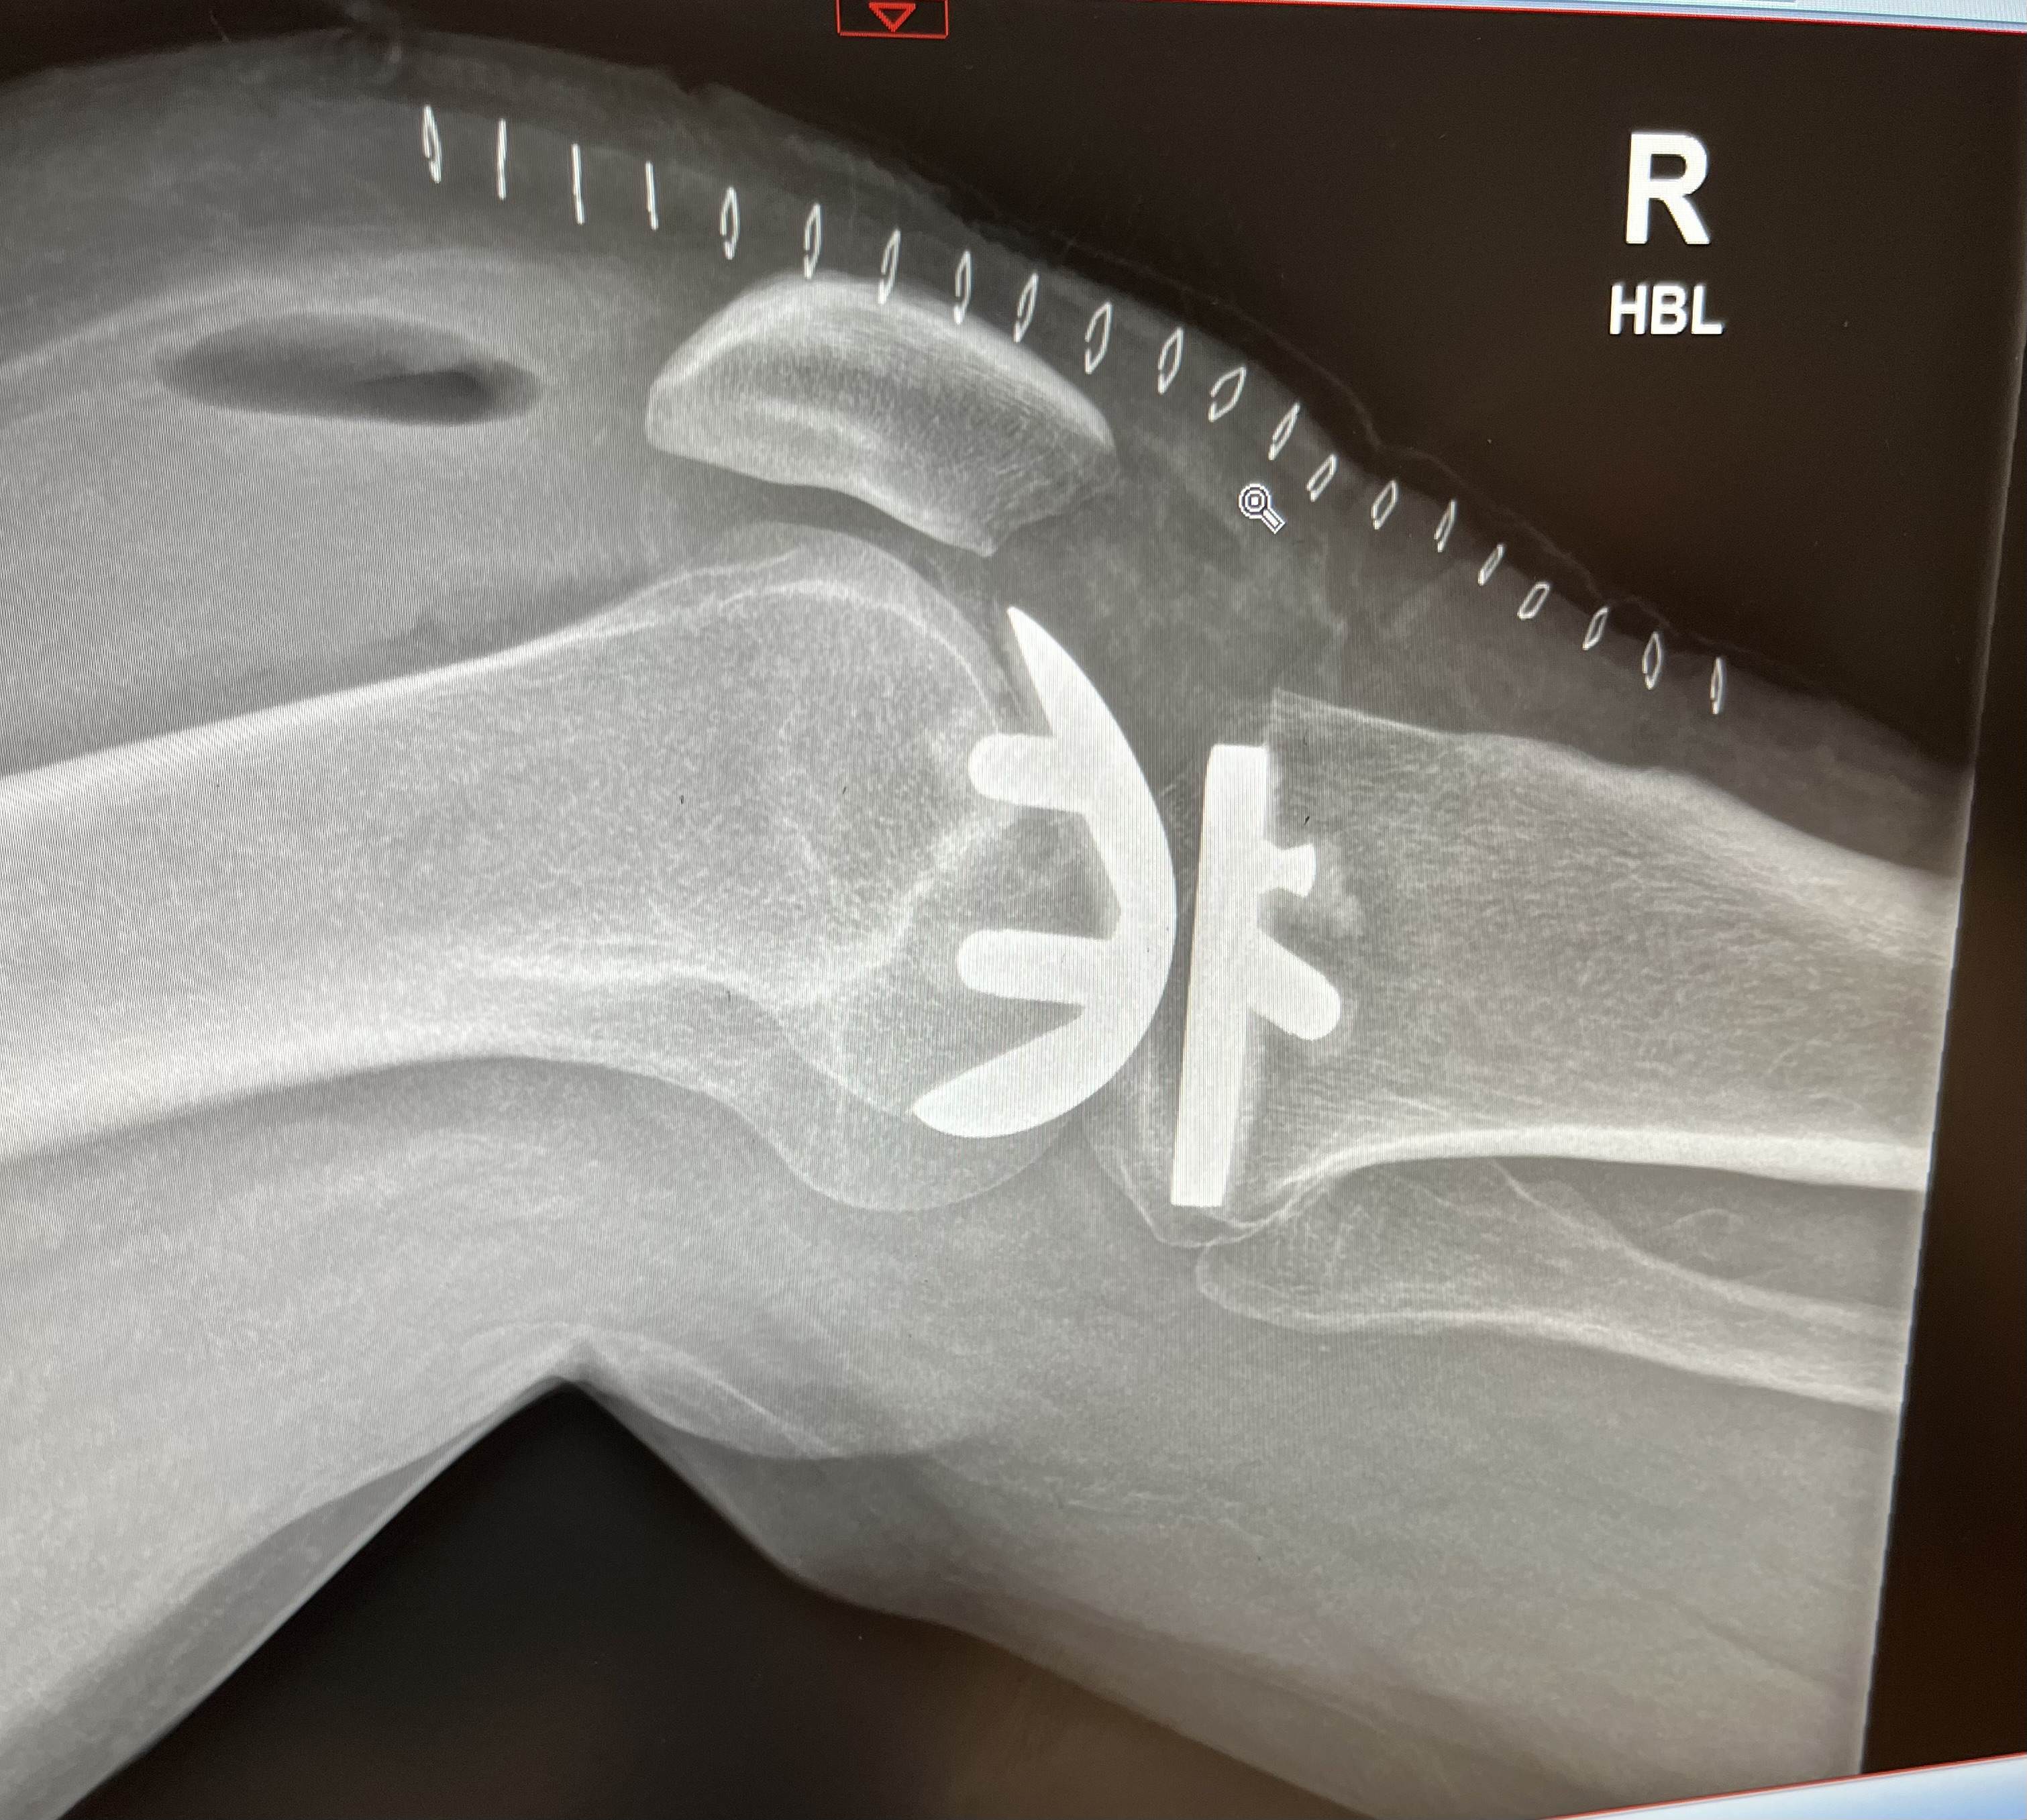

Then disaster struck when I tore my medial meniscus cartilage and discovered serious bone wear either side of it. After a minor surgery to try and sort the cartilage out it was obvious that I was going to need a knee replacement.

After several months of hobbling around and, in the end, being unable to walk more than 200m, the knee got replaced.